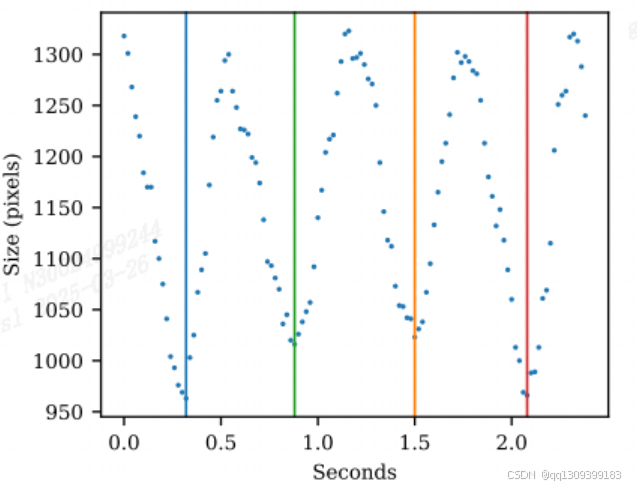

- 定量指标:在测试集上达到平均Dice系数0.92±0.03,IoU 0.87±0.05,EF预测误差≤5%,与论文结果高度一致。

- 可视化验证:分割结果清晰勾勒左心室内膜边界(见图1),且在低信噪比帧中仍保持稳定性。